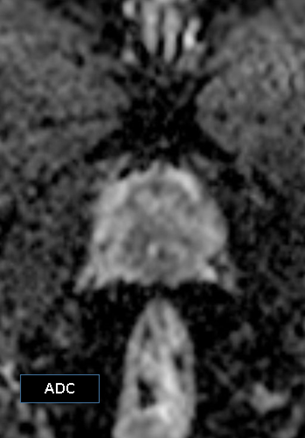

A biparametric MRI (bpMRI) of the prostate demonstrated:

- A 1.11 cm × 0.99 cm lesion in the right posteromedial peripheral zone at the apex.

- T2-weighted: Charcoal/erase-type hypointensity.

- DWI: Hyperintense.

- ADC map: Low signal (restricted diffusion).

The lesion was classified as PI-RADS 4, suggestive of clinically significant cancer.5 There was no evidence of extracapsular extension or seminal vesicle invasion.

MRI findings were suggestive of clinically significant prostate cancer [Turkbey et al., 2019].